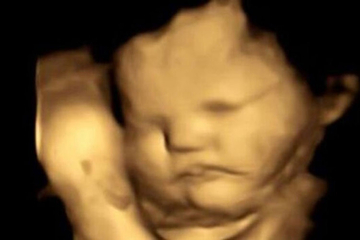

Zanimljivosti I nerođene bebe u majčinim stomacima „slažu face“ kada probaju kelj 22.09.2022. | 19:07